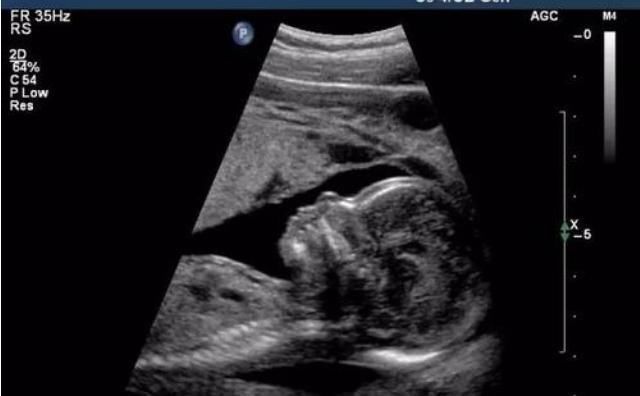

去医院做产检,医生说,孩子看起来就是很好动的,一会用手抓脸,一会用手挠屁股,都看不到脸。宝妈居然说孩子像她一样活泼好动,但是医生却说,不能留了,因为看到了孩子是唇腭裂。